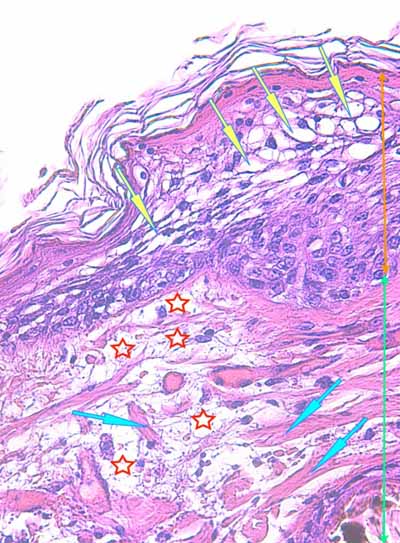

Photo 3 (Hémalun Eosine X 100) : l’épiderme se désengrène, une vésicule

sous-épidermique se forme. Le derme superficiel est œdémateux. Deux plages cellulaires dermiques

sont en étroit rapport avec des annexes folliculo-sébacées, dont une apparaît rompue.

Légendes de la Photo 3 :

- Ovales jaunes : plages cellulaires inflammatoires dans le derme périannexiel

- Flèche turquoise : follicule pileux rompu en rapport avec une plage inflammatoire

- Flèches jaunes : épiderme fragilisé qui se désengrène du derme

- Double flèche orange : épaisseur épidermique

- Double flèche verte : épaisseur dermique

- Double flèche bleue : épaisseur hypodermique

- Flèche orange : une vésicule sous-épidermique se forme

Photo 4 (Hémalun-Eosine X400) : l’épiderme montre des lésions d’œdème cellulaire

et de ballonnisation des acanthocytes, aboutissant à une dégénérescence réticulaire.

Le derme superficiel est œdémateux. Les fibres de collagène sont dilacérées par l’œdème.

Légendes de la Photo 4 :

- Flèches turquoises : fibres de collagène du derme

- Flèches jaunes : œdème et ballonnisation des acanthocytes épidermiques = dégénérescence réticulaire de l’épiderme

- Étoiles rouges : œdème dermique